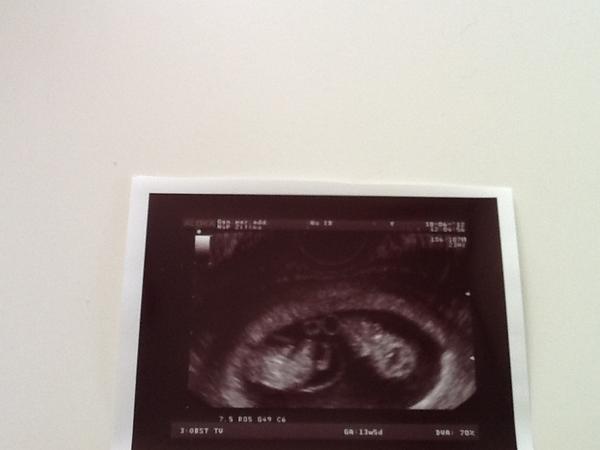

@kkatka113 Ahojky moja, ako sa mate? co miminka v brusku? my sme boli dnes na sone a su to jednovajecne zo spolocnou placentou a vonkajsim vakom ale kazde maju svoj vnutorny vak 🙂 🙂 🙂 jeej boli nadherne, videla som jednemu nozicky, rucicky, akurat sa prehadzovalo a to druhe si pekne spinkalo 🙂 🙂 no nadherny pocit 🙂 pripajam fotecku 🙂